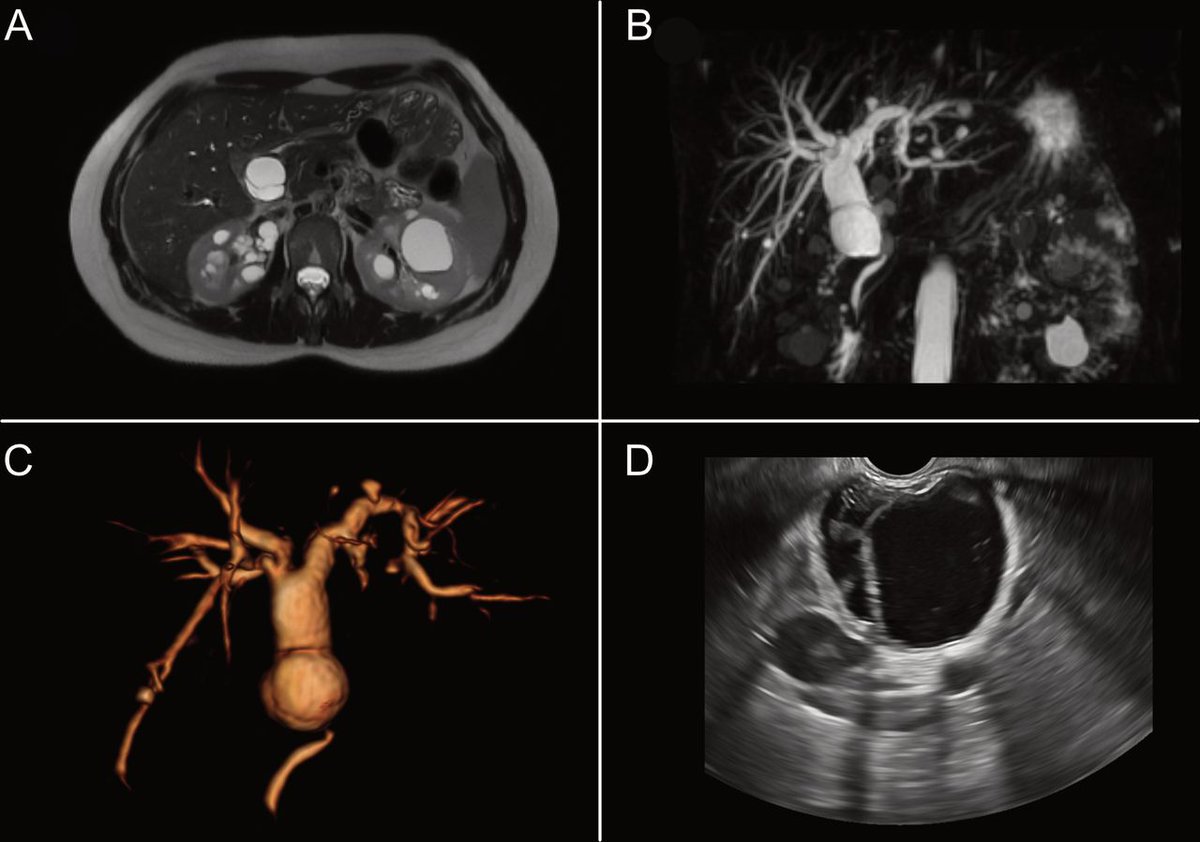

@ManualOMedicine

Manual Of Medicine

7 days

A 30 y/o man with a 15-month history of intermittent discomfort in the right upper quadrant of the abdomen. The physical examination revealed hepatomegaly with a palpable hepatic mass. - What is the diagnosis ? #medtwitter #foamed #usmle